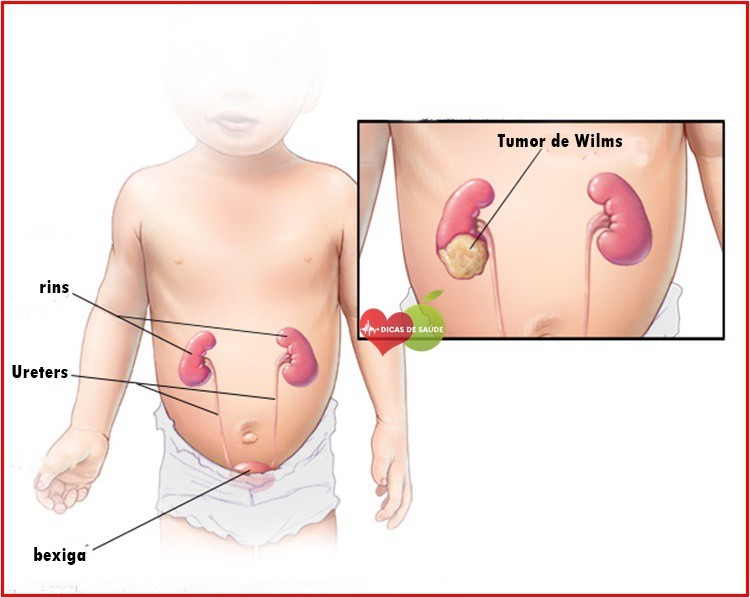

O Tumor de Wilms – O que é, Causas e Tratamentos que não devemos ignorar. Além disso, o Tumor de Wilms é um tipo raro de câncer de rim que afeta principalmente crianças. O câncer ocorre quando as células anormais em seu corpo se multiplicam de maneira incontrolável. Isso pode acontecer em qualquer idade, mas alguns tipos de câncer são exclusivos da infância.

O tumor de Wilms, também conhecido como nefroblastoma, é um desses câncer. Menos de uma em cada 10.000 crianças é afetada pelo tumor de Wilms nos Estados Unidos. Aproximadamente 500 crianças são recém-diagnosticadas a cada ano.

Embora raro, o tumor de Wilms é o tipo mais comum de câncer de rim em crianças e o quarto tipo mais comum de câncer infantil em geral. O tumor de Wilms é geralmente diagnosticado em crianças com cerca de 3 anos de idade. É raramente visto ou diagnosticado após a idade de 8, mas pode ocorrer em crianças mais velhas e adultos. Então, confira Tumor de Wilms – O que é, Causas e Tratamentos.

Sintomas do Tumor de Wilms: A condição ocorre com maior freqüência em crianças com idade média de 3 a 4 anos. Os sintomas do tumor de Wilms são semelhantes aos de outras doenças infantis, por isso é importante consultar o seu médico para um diagnóstico preciso. Crianças com tumor de Wilms podem apresentar os seguintes sintomas:

Causas Tumor de Wilms: Não está claro o que exatamente causa os tumores de Wilms. Até agora, os pesquisadores não encontraram ligações claras entre o tumor de Wilms e os fatores ambientais. Esses fatores incluem drogas, produtos químicos ou agentes infecciosos, tanto durante a gravidez da mãe quanto após o nascimento.

Tratamento para Tumor de Wilms: Uma vez que este tipo de câncer é tão raro, as crianças com tumores de Wilms são geralmente tratadas por uma equipe de médicos, incluindo:

A maioria das crianças sofre uma combinação de tratamentos para Tumor de Wilms. A cirurgia geralmente é o primeiro tratamento utilizado para pessoas nos Estados Unidos. O objetivo da cirurgia é remover o Tumor de Wilms.

Em alguns casos, o Tumor de Wilms não pode ser removido porque é muito grande, ou o câncer pode ter se espalhado para ambos os rins ou nos vasos sanguíneos. Se assim for, seus médicos podem primeiro usar quimioterapia ou terapia de radiação (ou ambos) para tentar encolher o tumor antes da cirurgia.

Seu filho pode sofrer mais quimioterapia, radioterapia ou cirurgia se o Tumor de Wilms não for completamente removido pela primeira vez. Os medicamentos específicos e a extensão do tratamento prescrito variam dependendo da condição do seu filho.